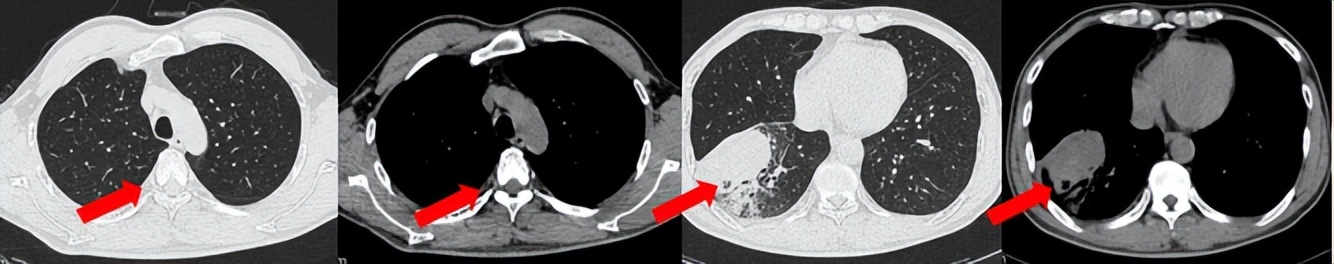

55岁男性,无吸烟史,有饮酒嗜好。2024年11月常规体检胸CT:左肺上叶占位性病变,大小约2.7×2.4cm,恶性可能大;左肺、左侧叶间胸膜及胸膜下多发微小结节,转移待除外。左侧胸腔积液,部分骨质改变。2024年12月初肺穿刺活检,病理:(肺)腺癌。NGS基因检测:CCDC6-RET(exon1-exon12)融合突变阳性(丰度:13.21%)。PD-L1表达阳性(TPS=35%,CPS=45)。

临床诊断:左肺上叶恶性肿瘤cT1cN2bM1a IVA期,肺门继发恶性肿瘤,纵隔继发恶性肿瘤,胸膜继发恶性肿瘤,胸腔积液。

治疗经过:2025.01开始口服普拉替尼(400mg,qd)。2025.03复查胸CT:左肺上叶、右肺上叶、左肺斜裂见多发实性结节影,长径范围约3-17mm,较大者大小约17mm×12mm,位于左肺上叶下舌段,可见分叶、毛刺、胸膜凹陷、棘状突起征象。纵隔内小淋巴结。评效PR,随访中。治疗期间未出现毒性反应。

2024.12

2025.03评效PR